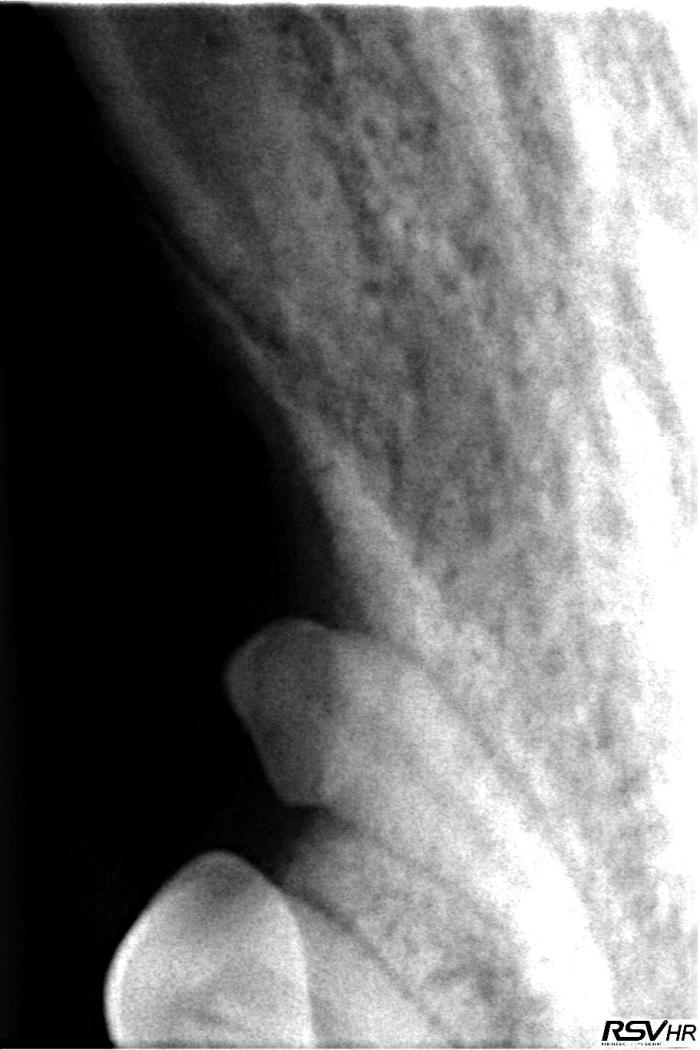

- Invaginación y radiolucidez periapical, sugiriendo infección, del diente 403 (ver Figura 3) (Figura4).

- Presencia del diente 404, incluido en el cuerpo mandibular, ventral a los dientes 406 y 407, con una forma acortada y aberrante (Figuras 5-7).

- Fusión de las raíces del diente 406, sin signos patológicos asociados (ver Figura 5).